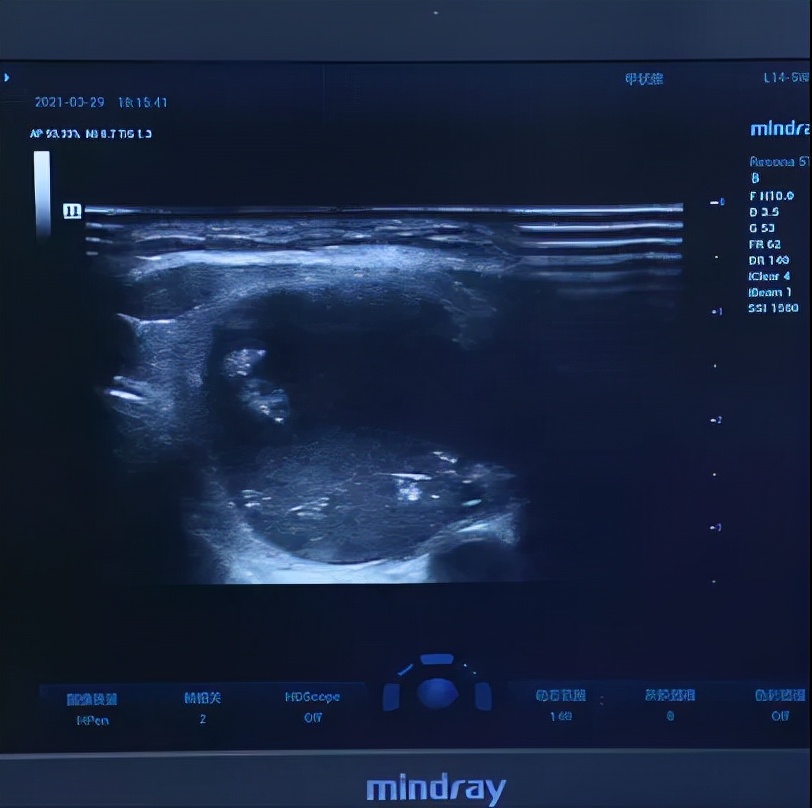

蒋女士的TSH指标到了53.7,比正常值高出12倍,APTO抗体达到了239.6,除了ATG指标是正常的,其他七项指标全部都异常。

而且甲状腺受多年甲亢影响,也呈现出弥漫性病变,包膜也不太完整了。